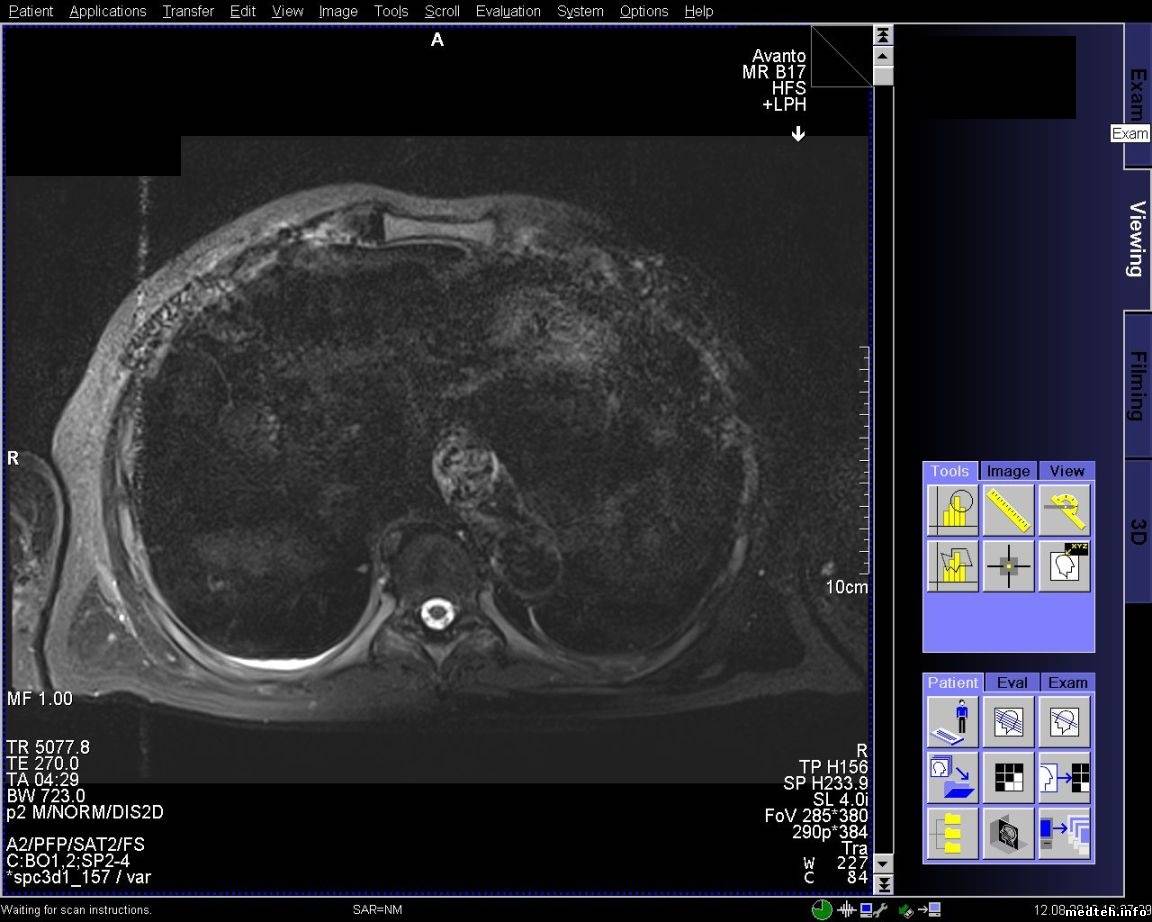

FedorM, спайк чек проходит, адвансед спайк чек не проходит. Выключал свет и инъектор, пробовал в разных комбинациях включать, адвансед спайк чек так и не проходит. Полосы появляются при обследовании с контрастом, но один раз было когда смотрели шею и коленку.

qa_1.pdf (135.4 Kb) · qa_2.pdf (126.1 Kb) · 5814388.jpg (197.7 Kb) · 8772789.jpg (220.4 Kb) · 6614537.jpg (206.3 Kb) · 3268821.jpg (226.4 Kb)

Всем доброго времени суток! Проблема с полосой так и остается актуальной. По снимку и протоколу было выяснено, что частота полосы ориентировочно 20-30 кГЦ, что соответствует частоте работы градиентов. Если гонять rf-noise, то помех (полос) не наблюдается. Полосы появляются на адвансед спайк чеке. Тест гоняли только на боди катушке и при этом если просто фантом лежит, то полоса может быть, а может и не быть. Но на паценте полоса стабильно стоит. Если положить на стол длинный провод и погонять адвансед спайк чек на боди катушке, то полоса стабильно проявляется. Следовательно пациент служит как бы антенной. Частота полосы в 20 кГц наводит на мысли, что неисправность в filter plate. Подскажите пожалуйста, что, где и как ещё можно посмотреть и проверить, если неисправность в filter plate, то как его проверить?